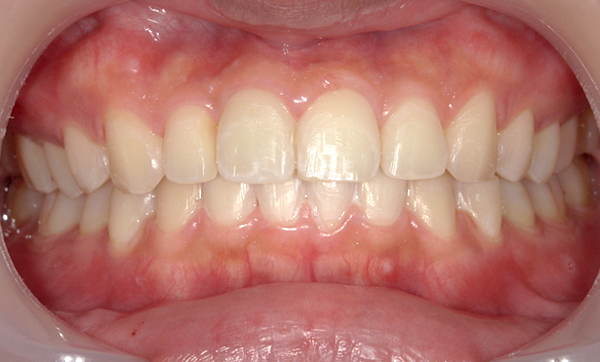

症例_009 「上下の前歯」症例

治療期間:7ヶ月金額:54万円+税20代女性捻転歯一部の反対咬合前歯のガタガタ

Before | After |

---|---|